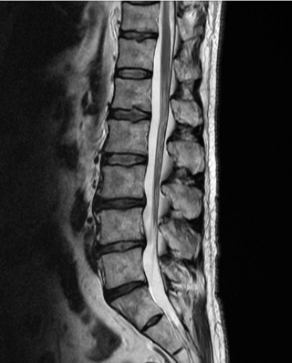

허리디스크를 정확하게 진단하기 위해서는 엑스레이로는 힘들며, MRI를 통해 검사해야 정확하게 볼 수 있습니다.

MRI가 몸에 좋지 않지만 허리 통증으로 엑스레이만 진행 할 경우 오진이 많아 지속적인 통증이 계속 된다면 허리디스크를 의심하고 MRI 검사를 한번 받아보시길 권유드립니다.